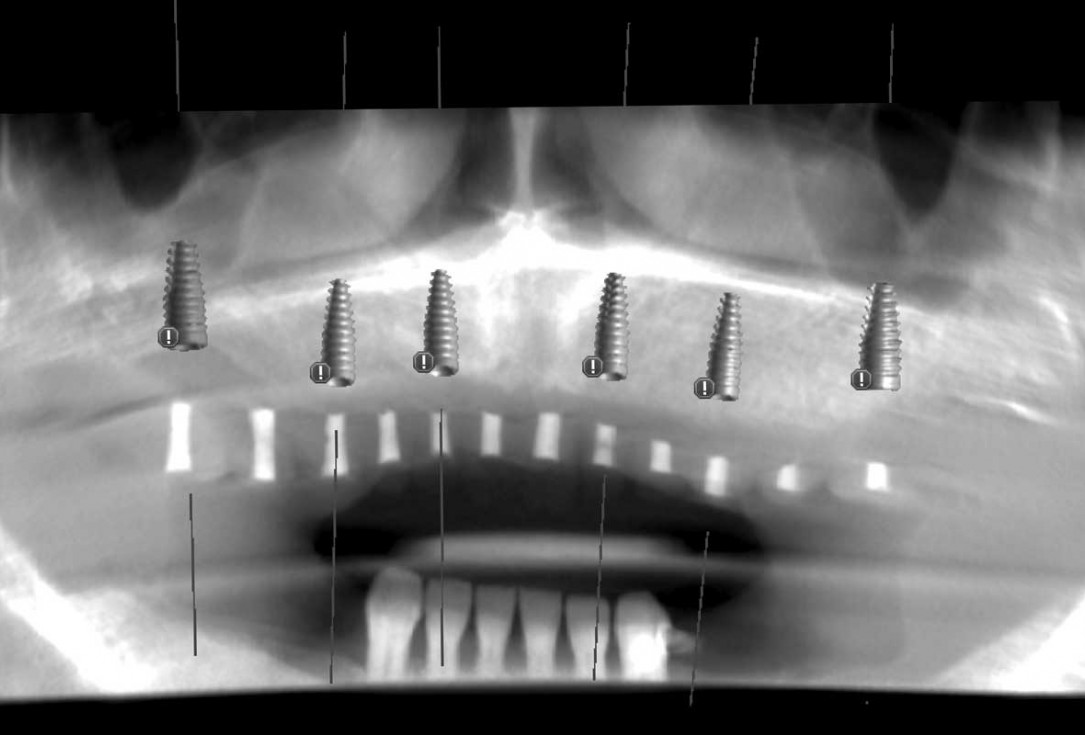

Full arch GBR using cerabone®, maxgraft® and Jason® membrane with simultaneous implantation of 6 Straumann® implants - Dres. A. Signorio and G. Molina

Initial x-ray showing bone loss around implants placed 5 years ago in another dental clinic